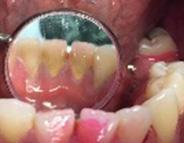

Figura 2. Vista lingual inferior dientes con sarro.

la bioplaca, el cual fue bajo según el IHOS 0.6 y el sarro se localizó en los OD Inferiores 32 y 42 por las superficies vestibular y lingual.

En la Figura 2 se ven los organos dentarios del 32 al 42 con sarro en la superficie lingual abarcando menos del tercio medio.